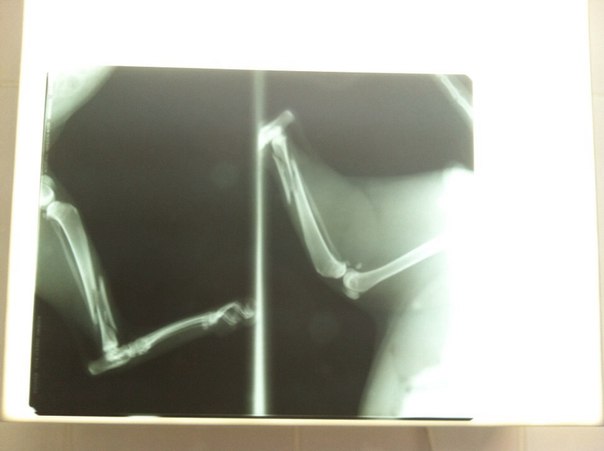

Котик слепой на один глаз, второй плохо видит! Машина переехала ему заднюю лапу, растрощив кость! бедный малышь долго лежал и плакал под забором пока ему кто-то поможет, и хоть всегда был диким, сейчас просто молил о помощи и дал себе помощь не сопротивляясь...

После рентгена стало понятно что кость раздроблена в нескольких местах и много осколков, нужна была очень сложная и не дешовая операция ((( усыпить кота очень жалко, слава Богу никакие органы не были задеты, но и без операции было не обойтись, такой перелом сам не срастется и только мучали бы страшные боли